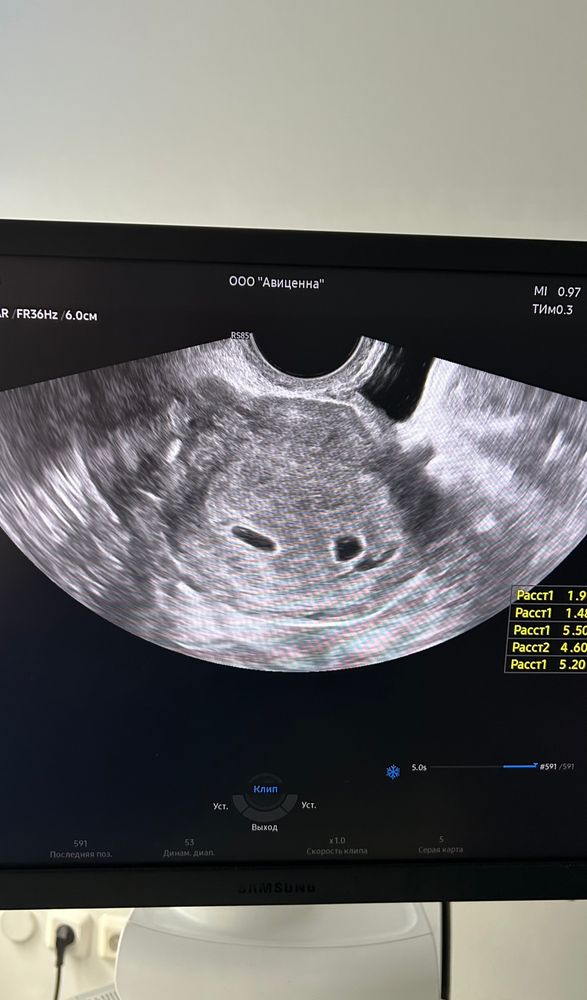

Помогите пожалуйста понять по узи, у меня двойня или близнецы?

Разнояйцевая двойня, дихориальная диамниотическая, у каждого свое плодное яйцо и плацента будет своя.